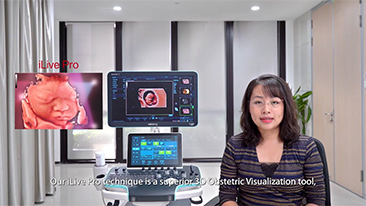

Geli?mi? ZST+ platformu ile desteklenen Nuewa'n?n tam kapsaml? ak?ll? ??zĂŒmleri, ?zellikle gebelik ?ncesi, gebelik ve do?um sonras? iyile?me sĂŒre?lerinde kad?n sa?l???n? iyile?tirmek, seviyeleri giderek daha da artan klinik zorluklar?n ĂŒstesinden gelmek i?in kapsaml? ve verimli tan?lar sunmak ĂŒzere tasarlanm??t?r.